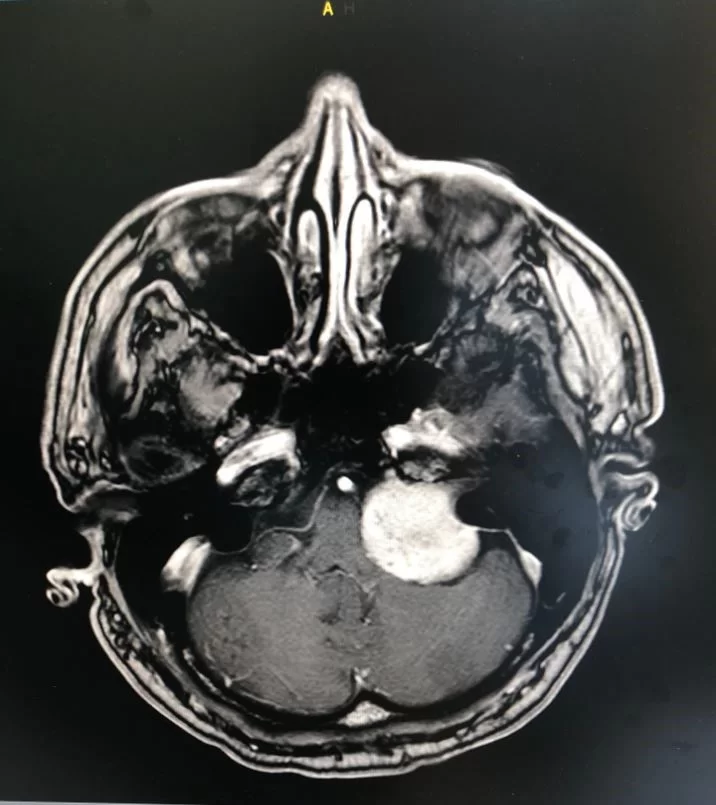

- Απεικονιστικές εξετάσεις, όπως μαγνητική τομογραφία ή αξονική τομογραφία – Η μαγνητική τομογραφία είναι η εξέταση εκλογής για τη διάγνωση των ακουστικών νευρινωμάτων (εικόνα 1). Η μαγνητική θα δείξει αν υπάρχει πράγματι ακουστικό νευρίνωμα, ποιό είναι το μέγεθός του, που ακριβώς εντοπίζεται, αν πιέζει κλπ. Η αξονική τομογραφία είναι συμπληρωματική της μαγνητικής.